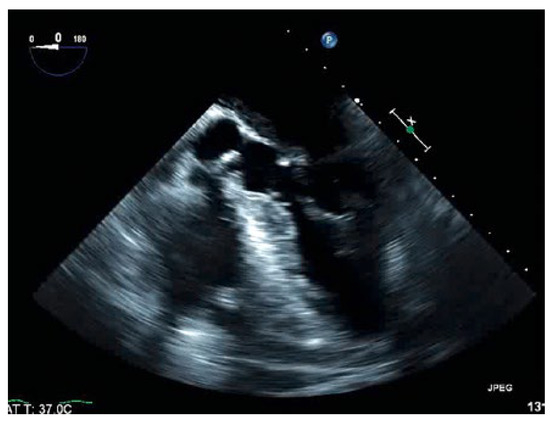

An 88-year-old man with a history of transient ischaemic attack, chronic kidney disease and primary hypertension presented with dyspnoea and was found to have large bilateral pulmonary emboli on a computedtomography angiogram of the chest [...]